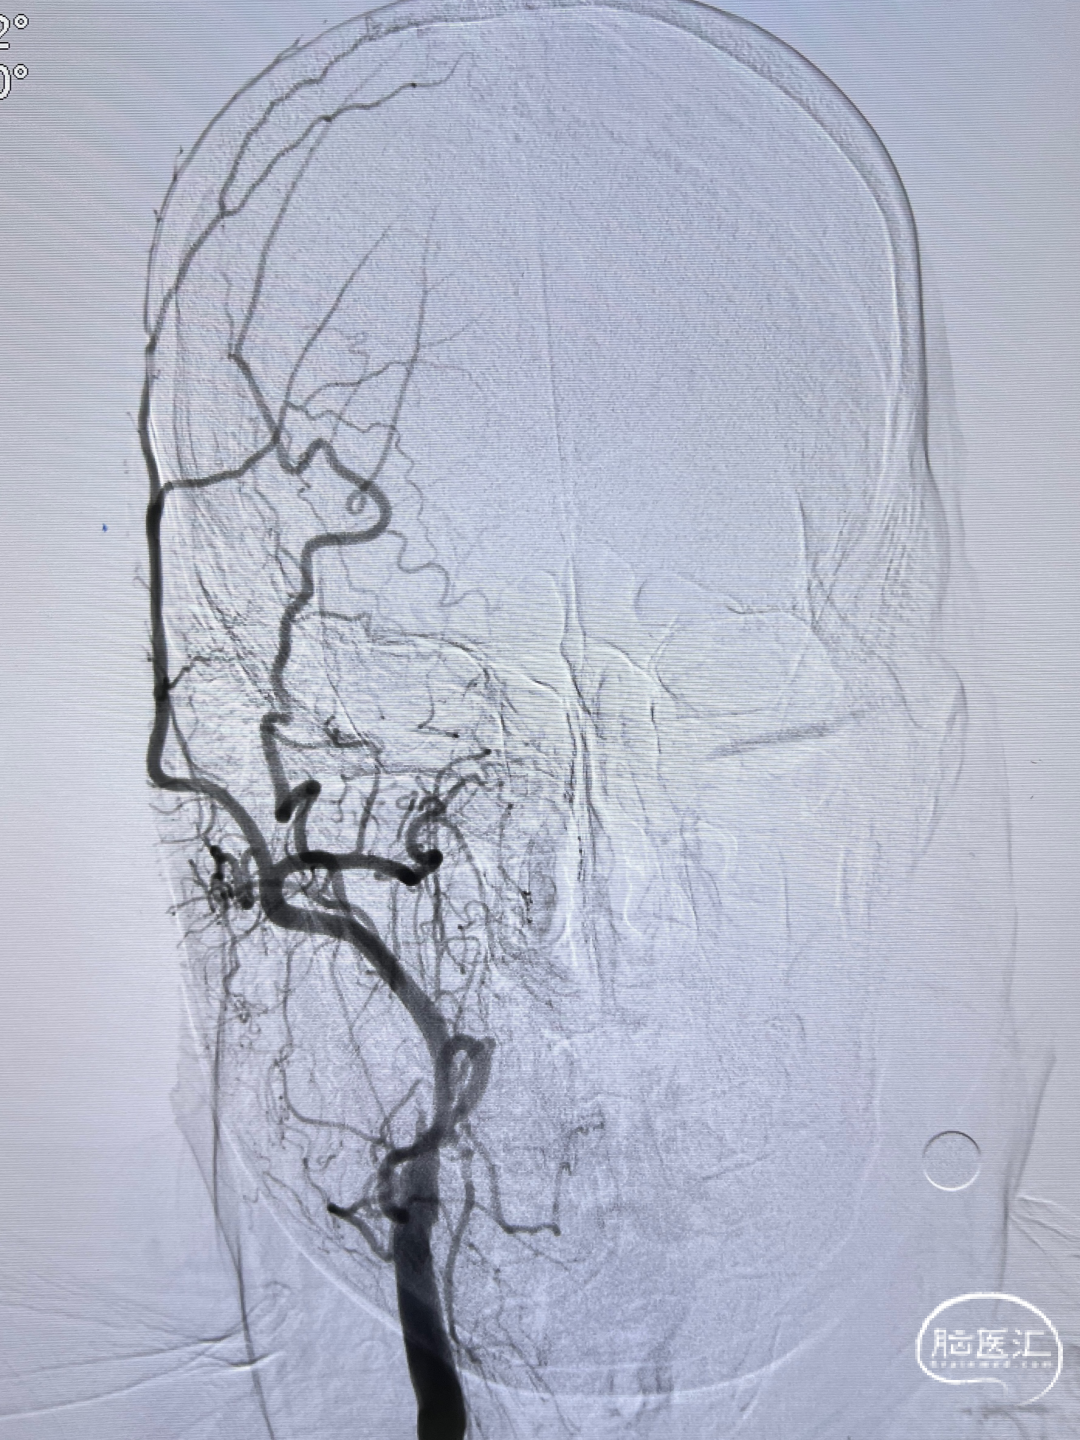

左侧颈内动脉重度狭窄,左侧大脑中动脉闭塞,通过前交通动脉向右侧大脑中动脉供血区代偿。

后循环造影。